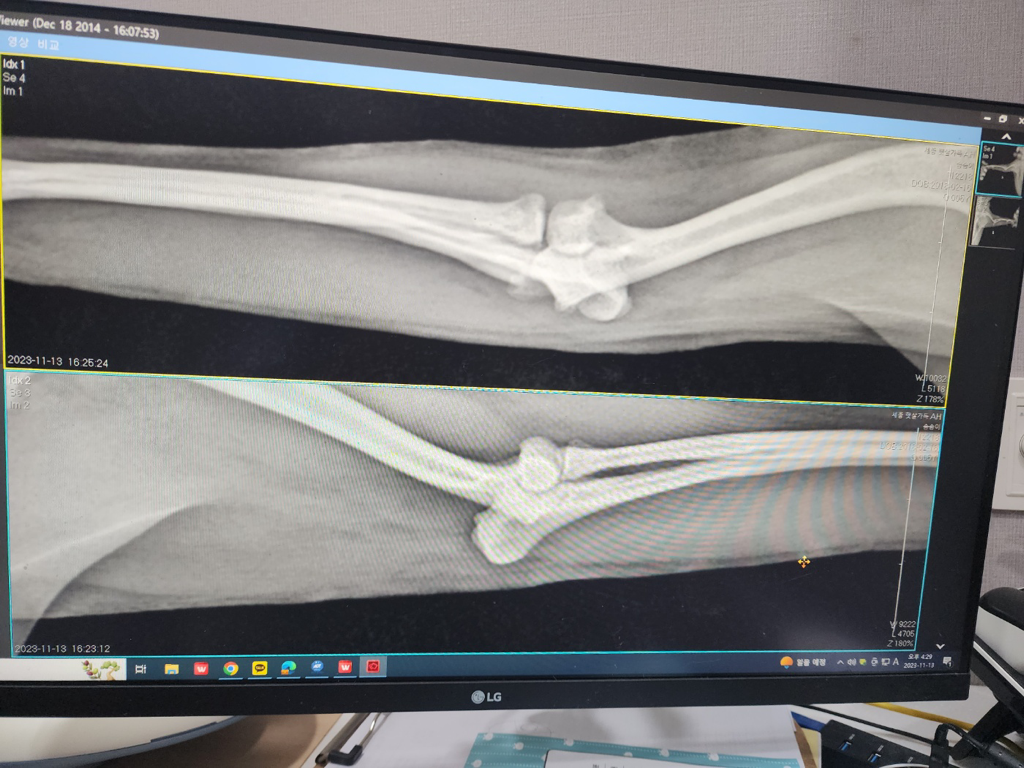

강아지 뼈 용해 이거 골육종인가요?

위 사진이 문제가 되는 다리입니다 강아지가 오른쪽 앞발을 들고만있고 디디지를 못하고 자꾸 절어서 병원에갔더니 뼈가 용해된건지 염증인지 골절인지 잘 모르겠다고 큰병원가보라고 하는데 이거 골육종인가요??골육종이라면 전이 가능성이 큰가요??ㅜㅜ내일 병원 갈거긴 한데 너무 걱정됩니다 ㅜㅜ 식욕은 있는편이예요

사진상 해상도의 문제로 정확한 소견을 알려드릴 수 없고 수의사가 소견을 어떻게 썻는지 모르겠지만, 병변의 변연이나 테두리가 지저분하거나 예쁘지 않은 경우는 많은 경우 결과가 좋지 못한 것으로 알고 있습니다.

뼈의 국소적 융해는 종양과 감염성 염증 둘중 하나인 경우가 대부분이나 감염성 염증은 물림 사고 등의 창상이 없는경우 일어나기 어려워

국소적인 골 융해가 보이면 골종양의 가능성이 매우 높은것으로 여깁니다.

하지만 확진을 위해서는 세포학 검사가 필수적으로 필요하니 동물병원에 가셔서 검진 잘 받으시고 진단 후 원인에 따른 치료를 받으시기 바랍니다.

외관상으로는 골육종 같지는 않습니다 통증이 있는 경우는 골육종 보다는 염증일 가능성이 있습니다. 염증을 일으키는 원인은 사진상으로는 정확히는 알 수 없습니다.